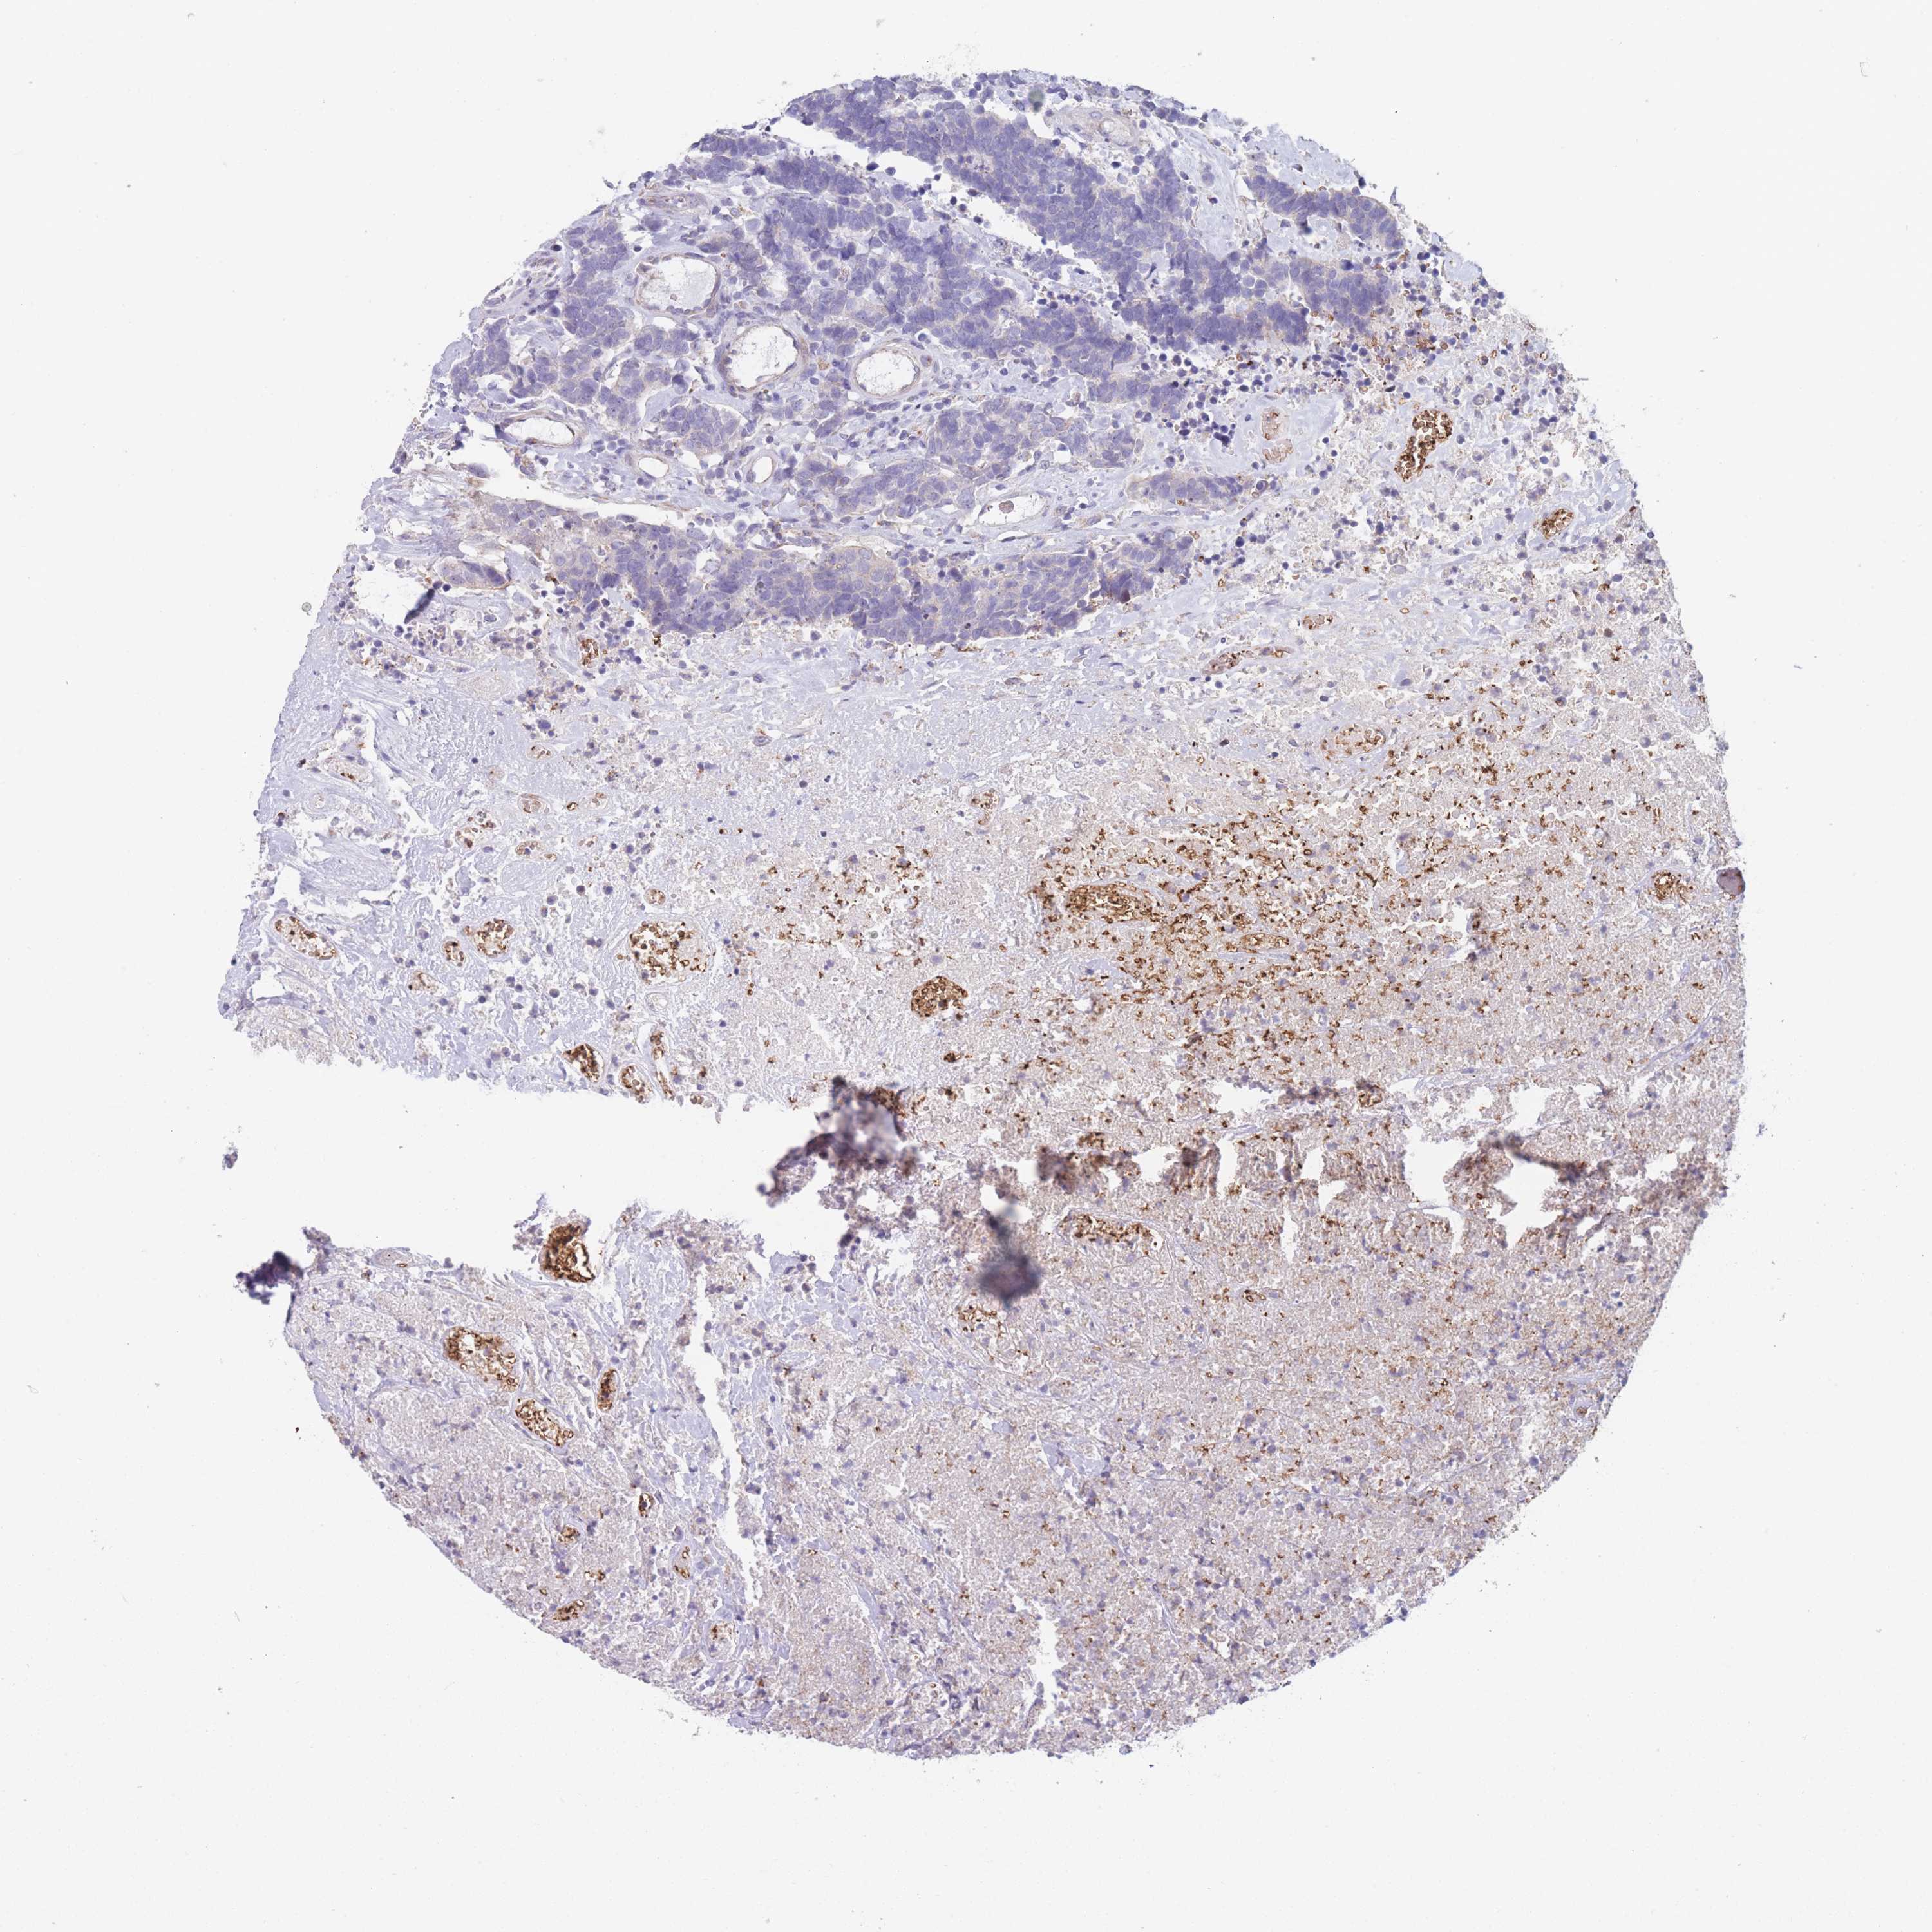

Neuroendocrine tumors

Human pathology

Carcinoid